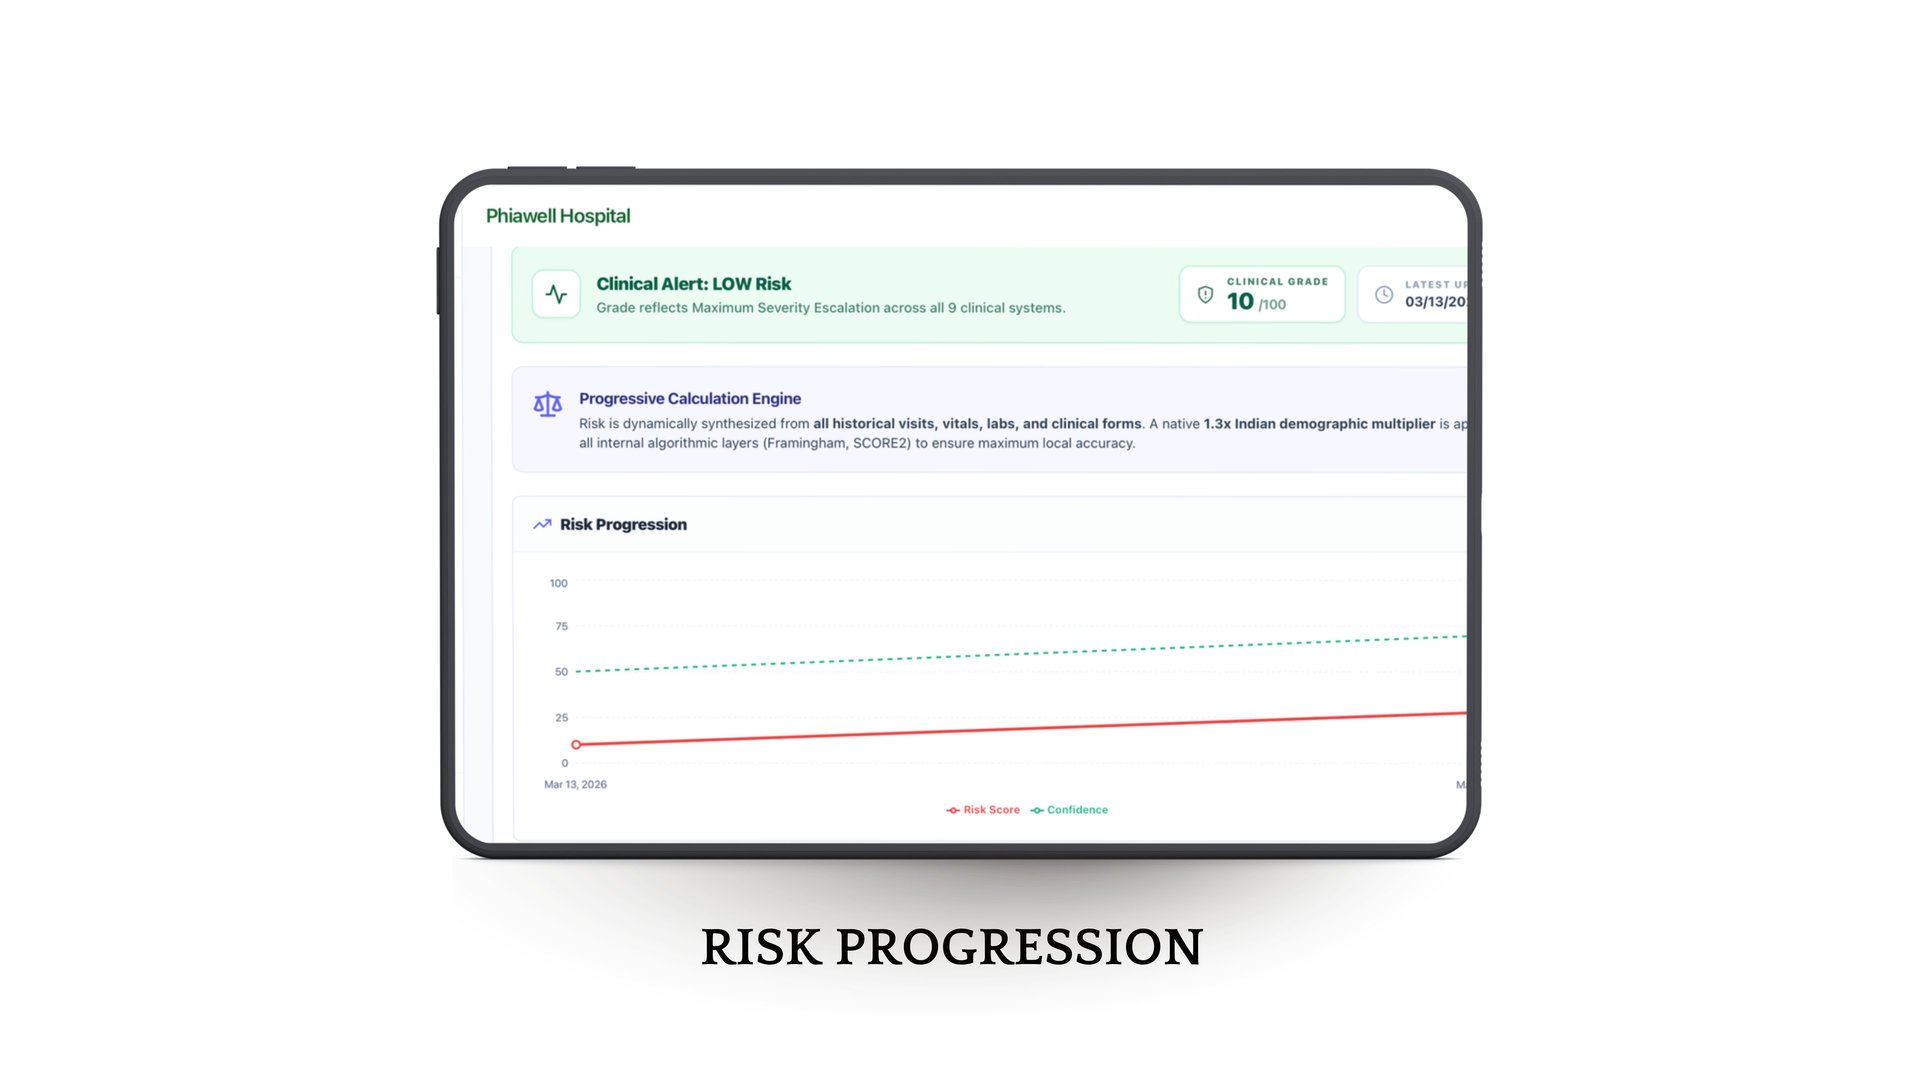

Intelligent Health Insights

With built-in risk assessment, smart analytics, and concise patient summaries, doctors can make faster, more accurate decisions while shifting towards preventive care.

Phia.Care's Risk Assessment Models

Phia.Care's Risk Assessment Models use clinically recognized algorithms, including WHO-based risk evaluation frameworks, to analyze patient screening data and generate structured health risk insights.

By evaluating vitals, demographics, and other screening parameters, the system creates a standardized risk profile for each patient and assigns a confidence score based on data completeness. This helps clinicians quickly understand potential health risks and support early, informed medical decisions.